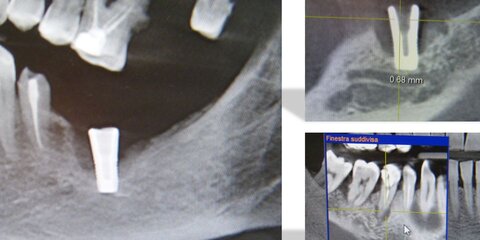

Durante questo webinar il relatore presenterà un selaer Bioceramico di nuova generazione (Avalon Neo Sealer Flo) e mostrerà le diverse tecniche di applicazione dei cementi bioceramici in modo da ottenere otturazioni tridimensionali ottimali senza estrusione incontrollata del sealer. Inoltre verrà spiegata la tecnica dell’apical plug in PD-MTA per la gestione degli apici irregolari e di ampio diametro.